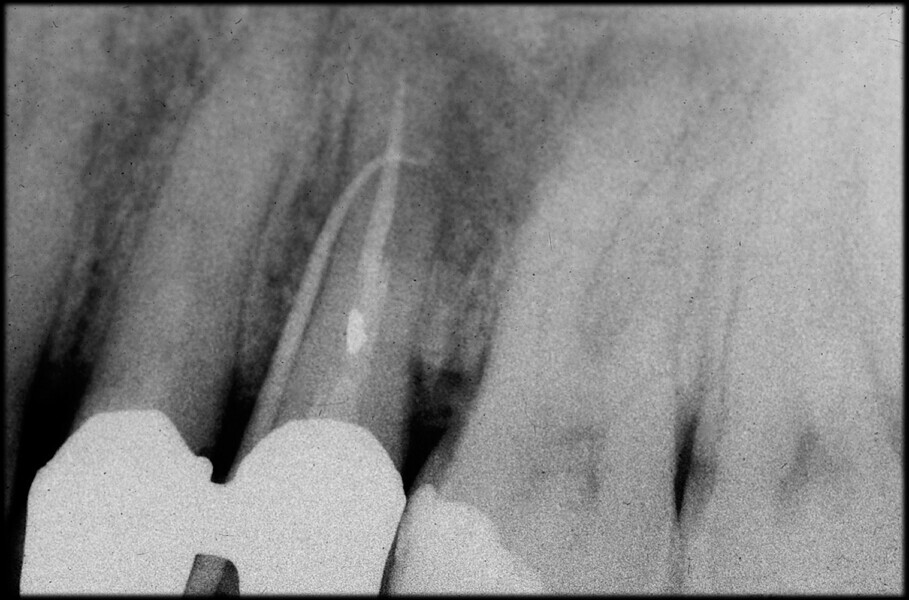

Use of 3D technology in the diagnosis and treatment of endodontic disease